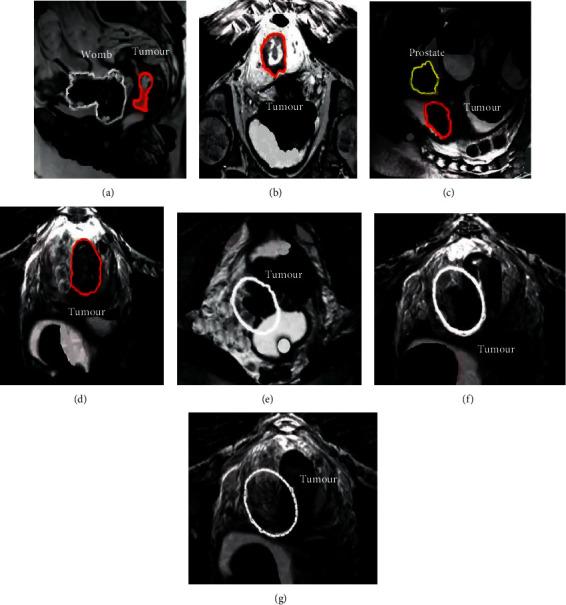

This study was carried out to explore the preoperative predictive value of dynamic contrast-enhanced magnetic resonance imaging (DCE-MRI) in extramural vascular invasion (EMVI) in patients with rectal cancer. 124 patients with rectal cancer were randomly divided into two groups, with 62 groups in each group. One group used conventional magnetic resonance imaging (MRI) and was recorded as the control group. The other group used DCE-MRI and was recorded as the experimental group. The diagnostic value was evaluated by comparing the MRI quantitative parameters of EMVI positive and EMVI negative patients, as well as the area under the curve (AUC) of the receiver operating characteristic curve (ROC), diagnostic sensitivity, and specificity of the two groups. The results showed that the Ktrans and Ve values of EMVI positive patients in the experimental group and the control group were 1.08 ± 0.97 and 1.03 ± 0.93, and 0.68 ± 0.29 and 0.65 ± 0.31, respectively, which were significantly higher than those in EMVI negative patients ( < 0.05). The AUC of EMVI diagnosis in the experimental group and the control group were 0.732 and 0.534 ( < 0.05), the sensitivity was 0.913 and 0.765 ( < 0.05), and the specificity was 0.798 and 0.756 ( > 0.05), respectively. In conclusion, DCE-MRI has a higher diagnostic value than conventional MRI in predicting EMVI in patients with rectal cancer, which was worthy of further clinical promotion.

本研究旨在探讨动态对比增强磁共振成像(DCE-MRI)在直肠癌患者外突血管侵犯(EMVI)术前预测中的价值。将 124 例直肠癌患者随机分为两组,每组 62 例。一组采用常规磁共振成像(MRI),记录为对照组。另一组采用 DCE-MRI,记录为实验组。通过比较 EMVI 阳性和 EMVI 阴性患者的 MRI 定量参数以及两组患者的曲线下面积(AUC)、受试者工作特征曲线(ROC)的诊断敏感性和特异性,评估诊断价值。结果显示,实验组和对照组 EMVI 阳性患者的 Ktrans 和 Ve 值分别为 1.08±0.97 和 1.03±0.93,0.68±0.29 和 0.65±0.31,均显著高于 EMVI 阴性患者( < 0.05)。实验组和对照组 EMVI 诊断的 AUC 分别为 0.732 和 0.534( < 0.05),灵敏度分别为 0.913 和 0.765( < 0.05),特异性分别为 0.798 和 0.756( > 0.05)。综上所述,DCE-MRI 对预测直肠癌患者 EMVI 的诊断价值高于常规 MRI,值得进一步临床推广。